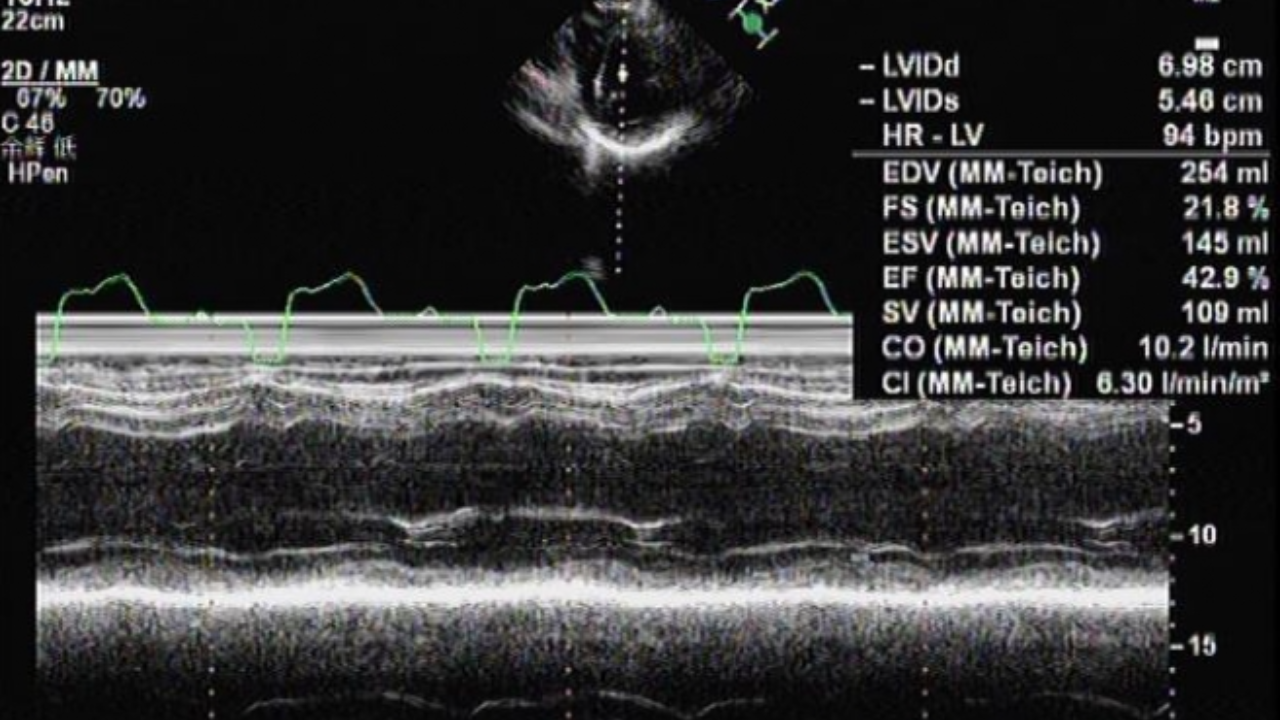

心超动图3:

心超:

讨论:1室间隔如跳跳鱼一般是何现象?2.结合心超、心电图、冠脉造影情况患者的诊断?